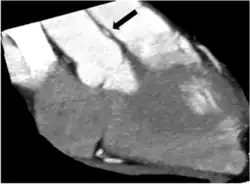

Cross-sectional computed tomography angiogram of RCA (between aorta and pulmonary artery) at the worst intramural site of compression (right anterior oblique projection). Black arrow = compressed intramural RCA.